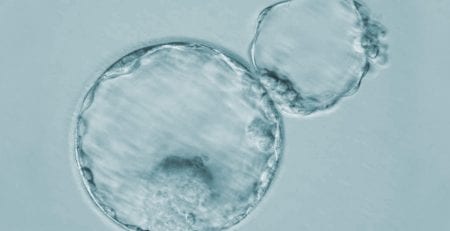

La inmunología reproductiva es un campo de estudio que analiza cómo reacciona el sistema inmunitario de una mujer cuando queda embarazada

Por lo general, su sistema inmunitario funciona al combatir las células invasoras que no reconoce porque no comparten su código genético. En el caso de un embrión, el sistema inmune aprende a tolerarlo aunque tenga un código genético diferente al de la madre.

Algunos científicos creen que en algunos casos de aborto espontáneo o infertilidad, el sistema inmunitario de la madre puede no aceptar el embrión debido a las diferencias en sus códigos genéticos.